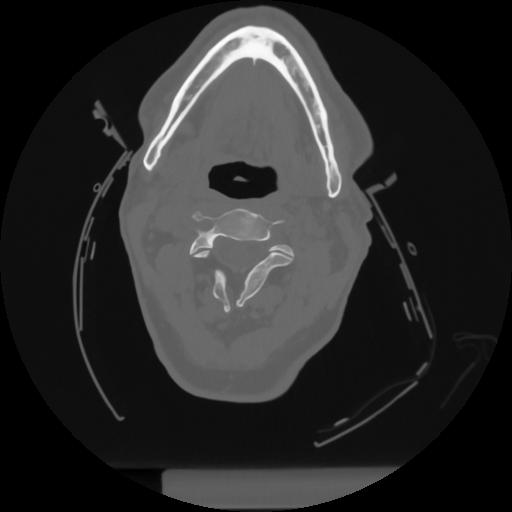

12 P.BLANDAS,,Vol,0.5,P.BLANDAS,,